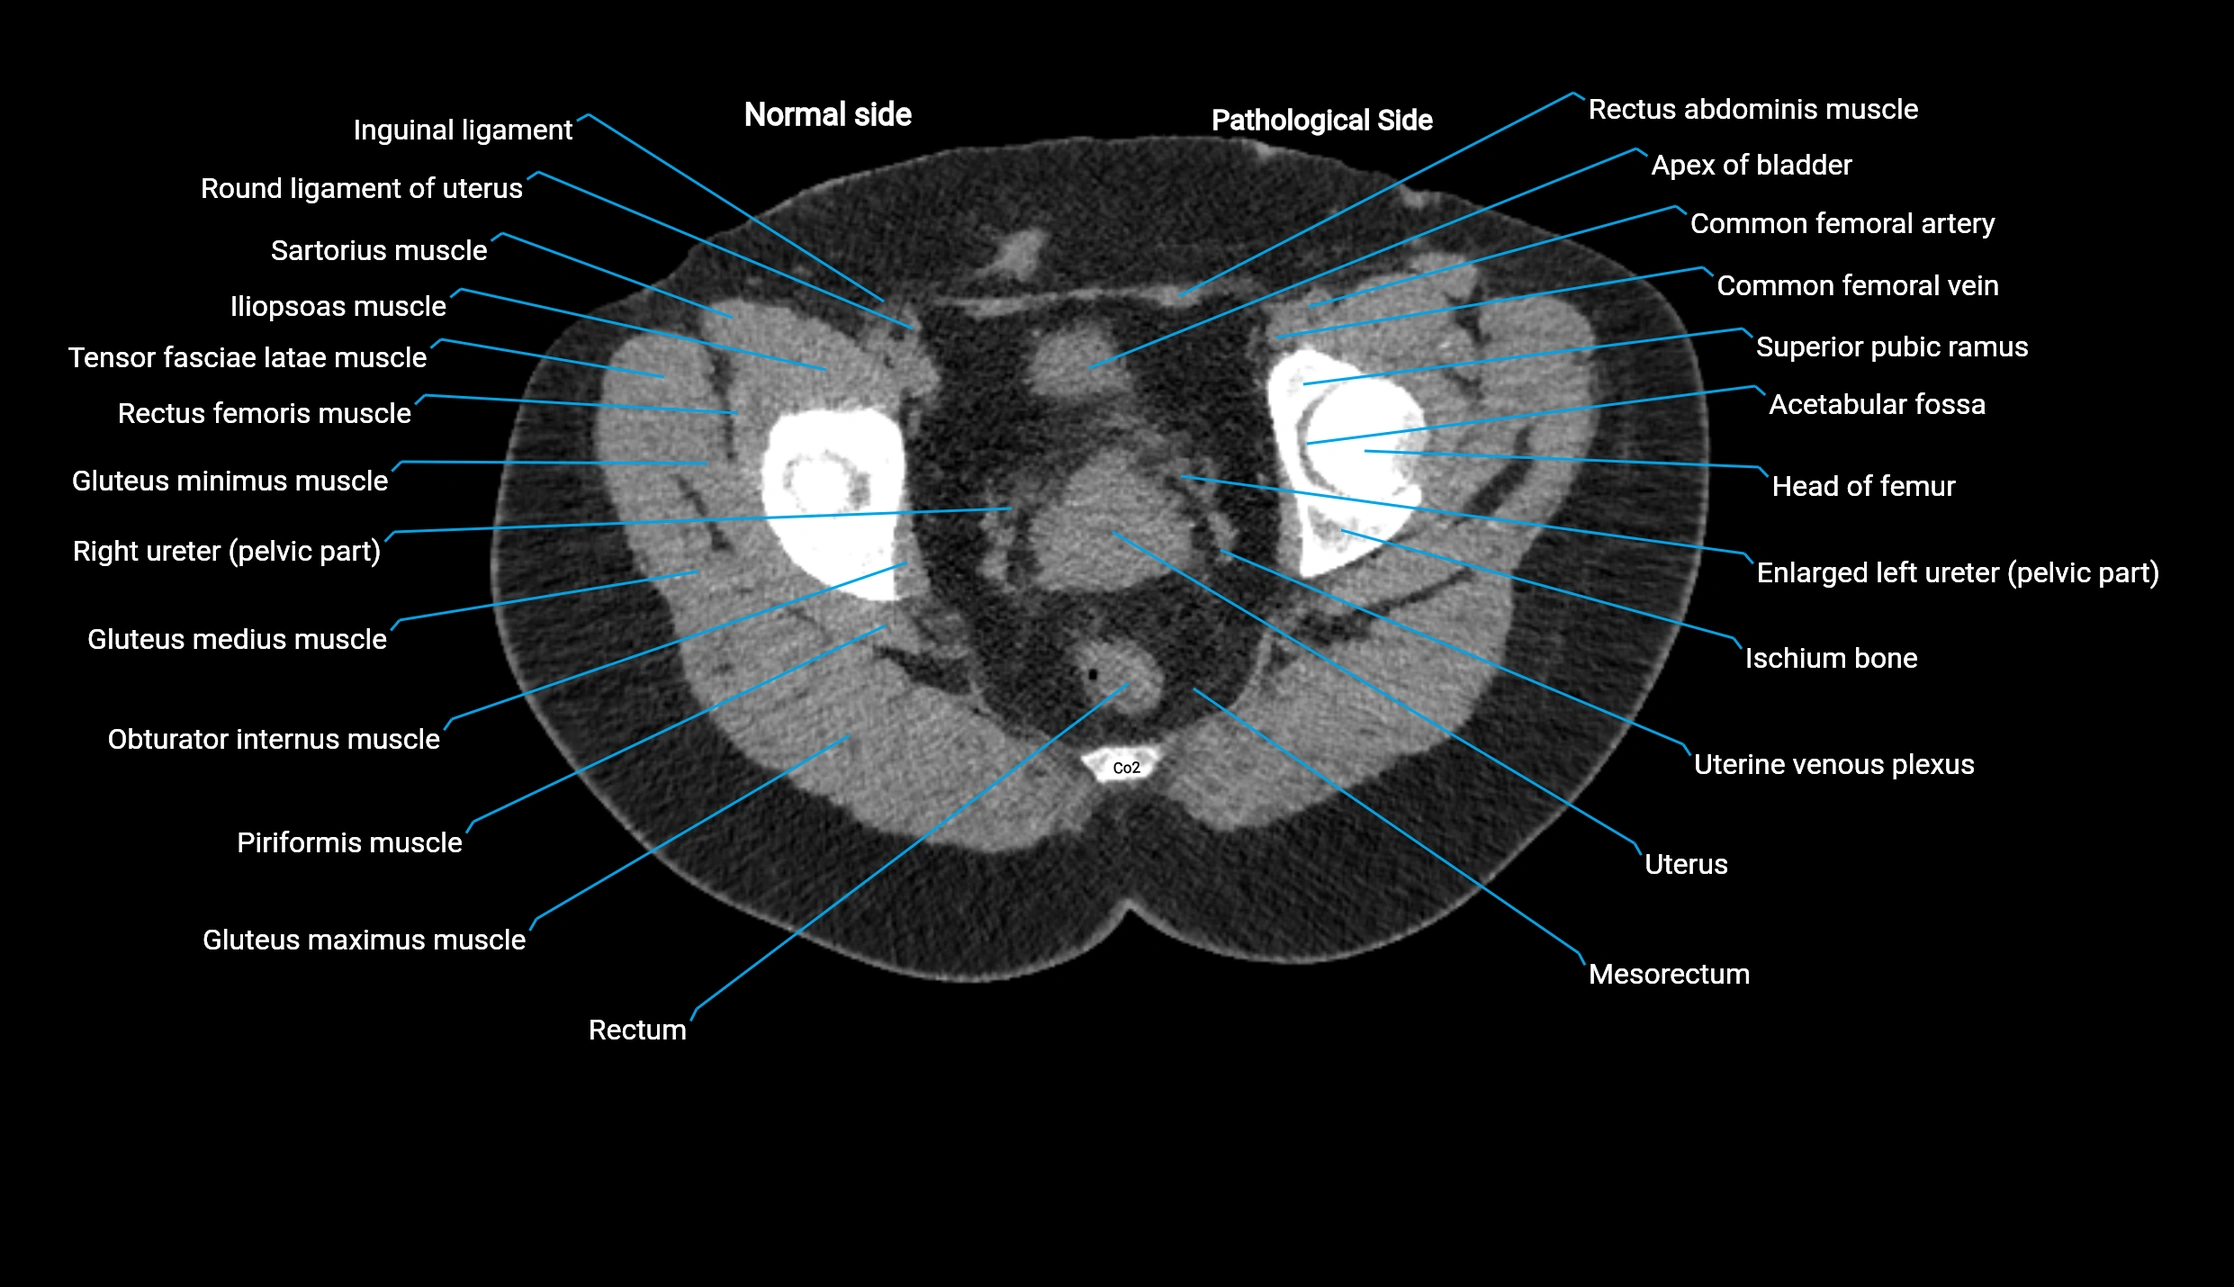

CT image

image